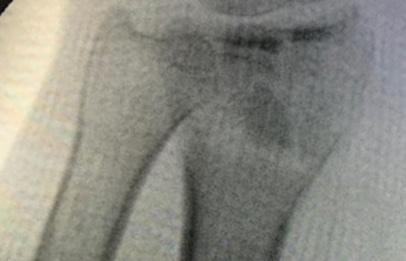

Cirugías de Húmero - Cirugías de Muñecas y Manos

Los procedimientos más comunes en cirugía de la mano son aquellos destinados a reparar traumatismos, incluyendo lesiones de tendones, nervios, vasos sanguíneos, y articulaciones; huesos fracturados; y quemaduras, cortes, y otros daños de la piel.